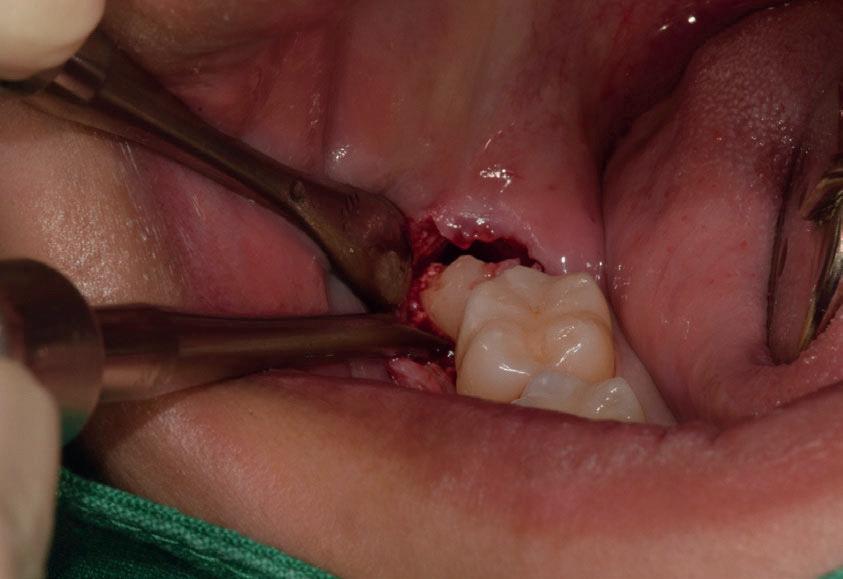

L’estrazione di un dente del giudizio incluso orizzontalmente, sfruttando questa tecnica con il manipolo dritto, richiede un’ulteriore rimozione di struttura dentale e di osso. Figg. 180-183

Per questo motivo, il lembo deve essere esteso fino al primo molare e bisogna avere una visione del sito chirurgico adeguata. Più il dente è inclinato orizzontalmente più la rimozione di osso vestibolare è necessaria.

Solitamente viene utilizzata una fresa a fessura dritta da manipolo per sezionare le radici, ma è preferibile usare una fresa rotonda laddove c’è la necessità di rimuovere l’osso alveolare attorno alla corona, come mostrato in fotografia. Figg. 184-187

In questo caso la separazione del periostio e la rimozione di osso vestibolare è quasi inevitabile per estrarre il #38.

Figg. 180-187 - Un caso di un’estrazione di un dente del giudizio, utilizzando il manipolo dritto. Fig. 180 Fig. 181 Fig. 182 Fig. 183 Fig. 184 Fig. 185 Fig. 186 Fig. 187